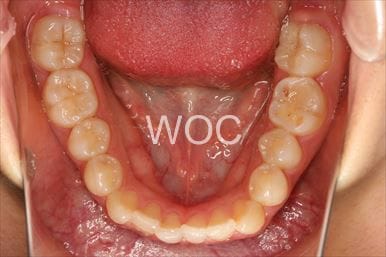

八重歯・叢生マウスピース型(カスタムメイド)矯正装置(インビザライン)

マウスピース型(カスタムメイド)矯正装置(インビザライン)を希望。ガタガタ(叢生)が強く上顎両側第一小臼歯抜歯か非抜歯のボーダーラインケースだったが、装置装着時間の協力も良く非抜歯で終了となりました。

- 年齢:35歳女性

- 主訴:ガタガタ

- 基本矯正料金:88万円

- 治療期間:2年6ヶ月

- 非抜歯

-